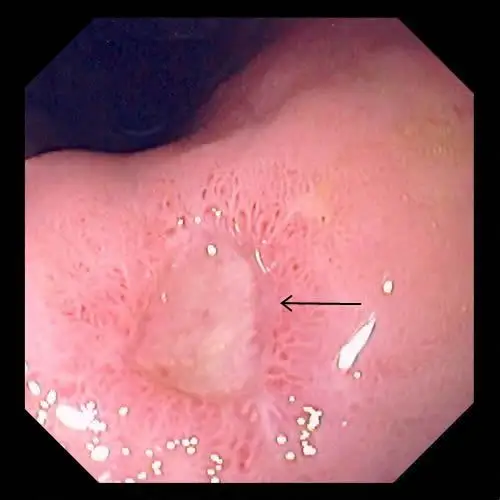

胃镜检查示:胃小弯4x5cm巨大溃疡,底部可见污苔及血痂,周边粘膜充血

胃镜发现胃溃疡时需要取活检明确溃疡的良恶性,内镜下的表现也可以